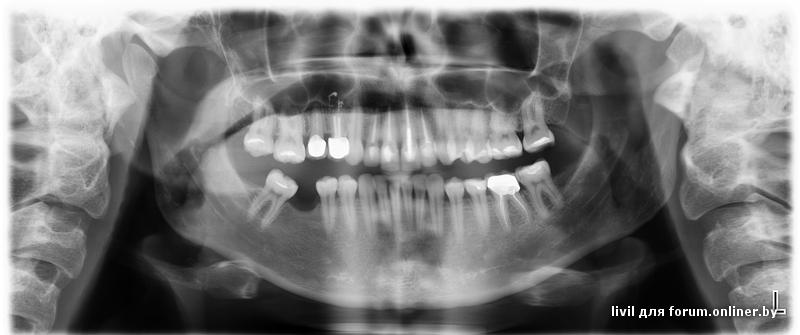

livil,

Стоит ставить в моем случае имплант или жить дальше без зуба?)

Сложно ответить на данный вопрос однозначно.

Есть методики исправления положения зуба

Принцип прост - за зубом в кость вкручивается временный микроимплантат и используя его, как опору исправляют положение моляра. Есть и другие ортодонтические методики. Правильнее сначала исправить положение зуба (длительный процесс), потом делать имплантацию. Объём кости для имплантации сложно оценить по плоскостному снимку. Вроде как объём костной ткани по вертикали есть. Однако, судя по давности удаления можно предположить значительное сужение альвеолярного отростка в вестибуло-оральном направлении. Чтобы точнее определить,хватит ли места под имплант (6) и какой будет имплант надо смотреть, что во рту очно плюс в помощь может быть современный метод рентгенологического обследования - компьютерная томография.

sniper1:Объём кости для имплантации сложно оценить

а какое мнение насчет наращивания кости костным материалом?

sniper1:Чтобы точнее определить,хватит ли места под имплант (6) и какой будет имплант надо смотреть, что во рту очно плюс в помощь может быть современный метод рентгенологического обследования - компьютерная томография.

Про выравнивание положения зуба ни один врач не говорил. Если так, это это все еще более усложняет (в т.ч. и по деньгам) процедуру.

Да, делала ЭКТ, кости достаточно, можно делать имплантацию. Вот только нужно ли?...